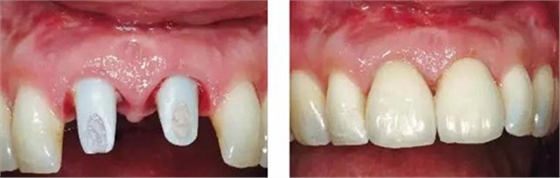

圖11、牙冠戴入1個月以后。軟組織外形良好,形成了良好的弧線形牙齦形態(tài)而沒有瘢痕。保持了原有的色素沉著的顏色和形狀。

圖12、種植術后1年顯示良好的美學效果。

圖14、最終修復體就位,冠頸部較窄。沒有任何牙齦和牙齦乳頭的退縮。

圖15、種植體植入后12個月的微笑相。